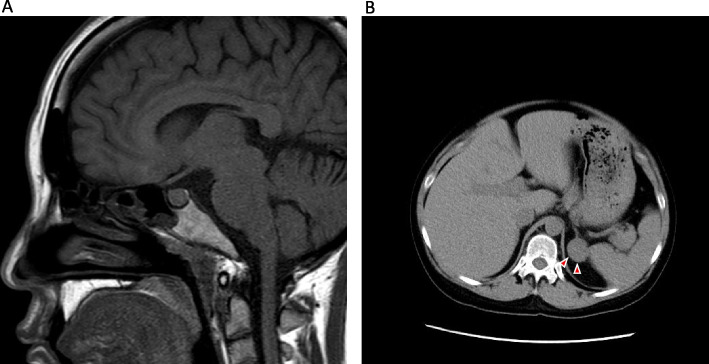

Case presentation: A 29-year-old woman with a history of pregnancy-induced hypertension developed severe hypertension, hypokalemia, and polyuria (6.6 L/day) during her 7th pregnancy. Laboratory findings showed elevated cortisol, suppressed adrenocorticotropic hormone (ACTH), and a 30-mm left adrenal mass, confirming adrenal CS. Despite potassium supplementation, persistent polyuria and fluid imbalance necessitated initiating desmopressin therapy at 27 weeks of gestation. The patient subsequently developed preeclampsia and underwent emergency cesarean section at 29 weeks, delivering a 1197-g infant with a very low birth weight. Polyuria resolved postpartum, and she underwent left adrenalectomy after discharge.